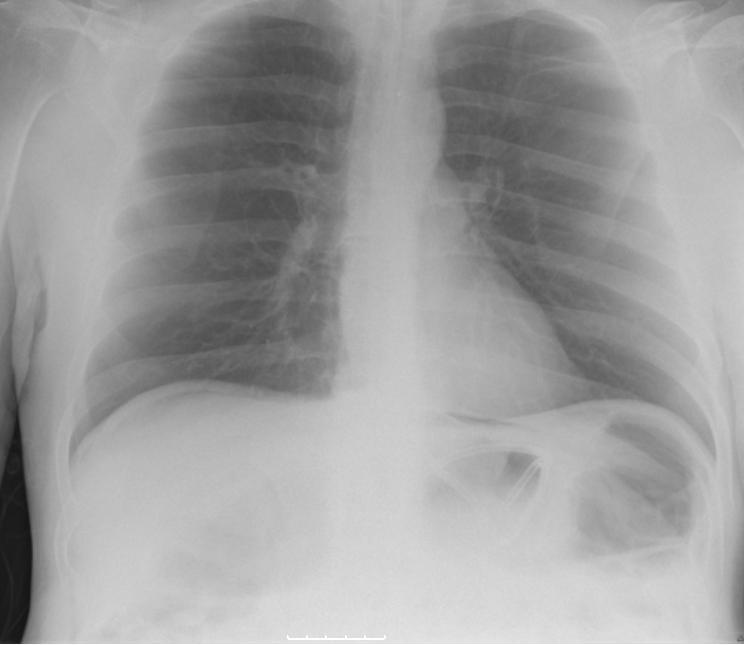

Een 52-jarige man meldde zich met klachten van misselijkheid, braken, buikpijn en persisterende diarree. De klachten waren een week na palliatieve chemotherapie ontstaan (intraveneus etoposide en cisplatine, oraal capecitabine). Patiënt kreeg deze chemotherapie voor peritonitis carcinomatosa bij een lokaal doorgegroeid maagcarcinoom. Bij lichamelijk onderzoek waren druk- en loslaatpijn in epigastrio en afwezige leverdemping bij percussie. Laboratoriumonderzoek toonde een verhoogd CRP (270 mg/l) en een gecompenseerde metabole acidose. Een thoraxröntgenfoto bevestigde ons vermoeden van vrij gas in de buikholte (klik op de afbeelding voor volledige weergave).